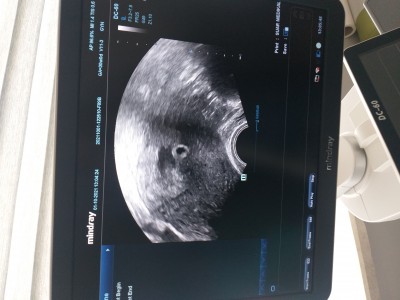

Tüp bebek ile hamile kaldim cuma günü keseyi gördük çok şükür  ama dr kaç haftalık olduğunu sormayı unuttum 25 ağustosta tedavim başladı 7eylul de yumurtam toplandı 10 eylülde 3. Gün embriyosu trasfer oldum ve çok şükür tuttu  son adet tarihim göre 5+5gun oluyorum ama cuma günü sadece kese gözüktü ici bomboş tu kaç kişiye gösterdiysem çok normal 1 hafta 10 güne görünmeye başlar dedi drum da ayın 15 de kalp atışını duymak icin çağırdı

image